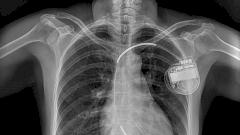

ИКД (имплантируемый кардиовертер-дефибриллятор) уменьшает опасность для жизни пациентов, у которых возможна внезапная остановка сердца. Однако что мешало распространению одного из самых важных изобретений XX века?